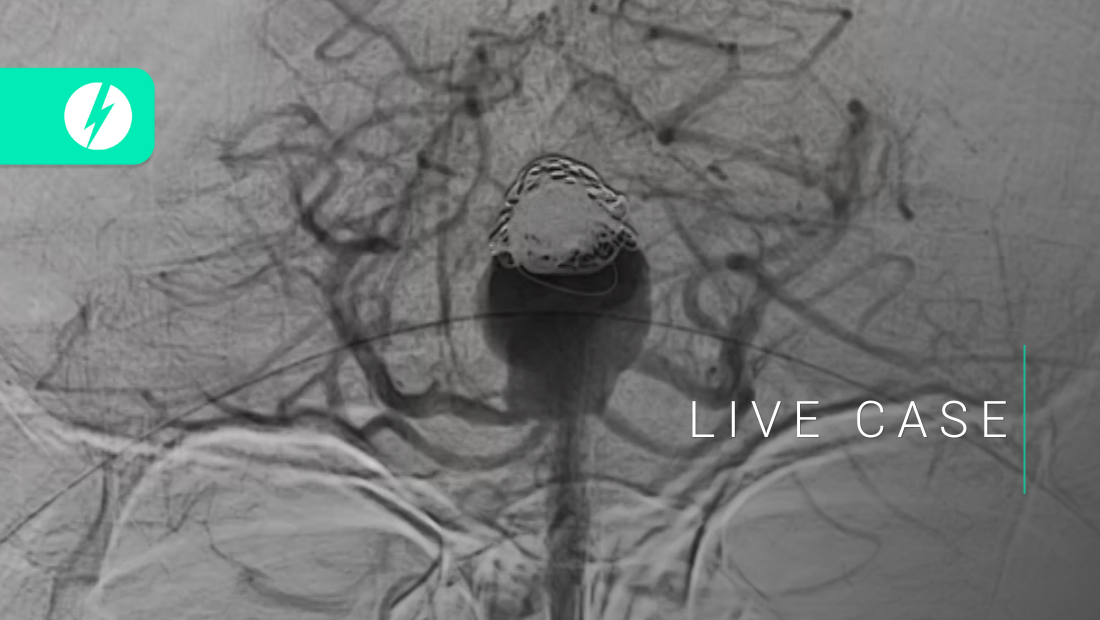

Recanalization of top-of-the basilar aneurysms after simple coiling - SLICE Next Frontiers 2022 - Samantha BIDOO

Extradural giant aneurysms - SLICE Next Frontiers 2022 - Greta REIKONEN